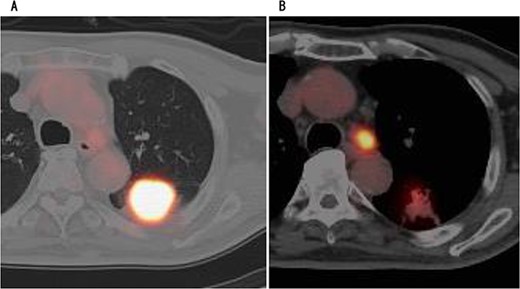

A 75-year-old male was referred to our hospital for preoperative examination of an abnormal chest shadow during orthopaedic surgery. Chest computed tomography (CT) revealed a mass nodule measuring 4.1 cm in S6 of the left lung, and the tracheobronchial lymph node (No 4 L) was enlarged (Fig. 1). Fluorodeoxyglucose positron emission tomography (PET) revealed abnormal accumulation with a maximum standardized uptake value of 20.4 at the mass, 9.4 at the lymph node and no metastases to other organs (Fig. 2). Based on the above findings, we diagnosed the patient with left lower lobe lung cancer (cT1bN2M0, c-Stage IIIA). The patient had no history of cardiovascular disease and was unaware of chest pain, such as an angina attack. We performed robot-assisted left lower lobectomy.

PET showed high accumulation in the mass (A) and lymph node (B).